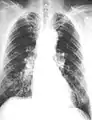

The abnormal chest x-ray and its interpretation remain the most important factors in establishing the presence of pulmonary fibrosis.[11] The findings usually appear as small, irregular parenchymal opacities, primarily in the lung bases. Using the ILO Classification system, "s", "t", and/or "u" opacities predominate. CT or high-resolution CT (HRCT) are more sensitive than plain radiography at detecting pulmonary fibrosis (as well as any underlying pleural changes). More than 50% of people affected with asbestosis develop plaques in the parietal pleura, the space between the chest wall and lungs. Once apparent, the radiographic findings in asbestosis may slowly progress or remain static, even in the absence of further asbestos exposure.[25] Rapid progression suggests an alternative diagnosis.

- Extensive fibrosis of pleura and lung parenchyma

- 61-year-old working industrially with asbestos for decades